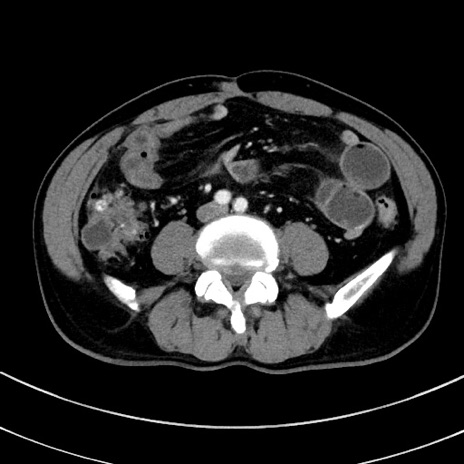

症例8(横断像)

冠状断像

【症例】 60歳代男性

【主訴】 黒色吐物

【現病歴】 4日前から嘔気自覚、2日前の朝食後にも嘔気あり、自分で手で嘔吐反射起こし嘔吐したところ血が混ざっていたため受診。

【既往歴】 5年前汎発性腹膜炎を伴う急性虫垂炎で手術、高血圧、前立腺肥大症、高脂血症

【身体所見】 腹部正中に手術癩痕あり 腹部平坦・軟圧痛なし膨満感あり

【データ】WBC 8400、CRP 4.54